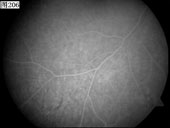

[组图]优秀眼底图片奖网上评选活动启动         ★★★

优秀眼底图片奖网上评选活动启动

优秀眼底图片奖应征作品展示